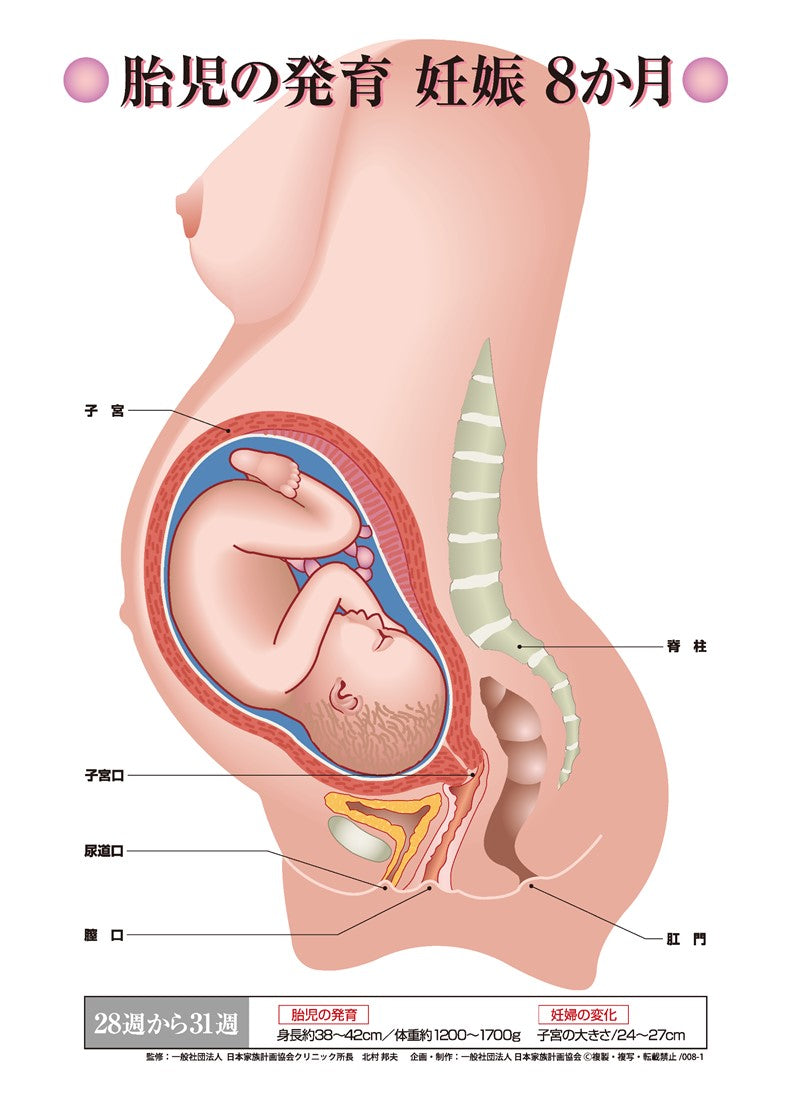

胎児の発育 妊娠8か月 – JFPA®オンラインショップ。

妊娠中の母体の変化と胎児の成長過程が描かれたパネル│W43076。